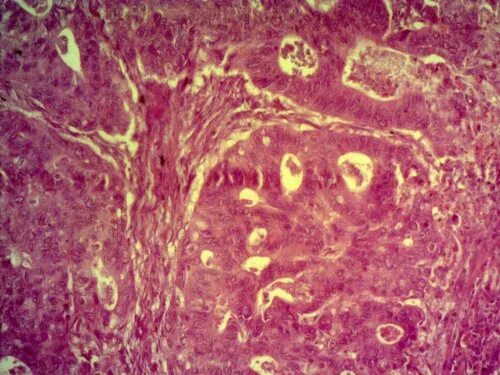

Высокодифференцированная аденокарцинома кишки